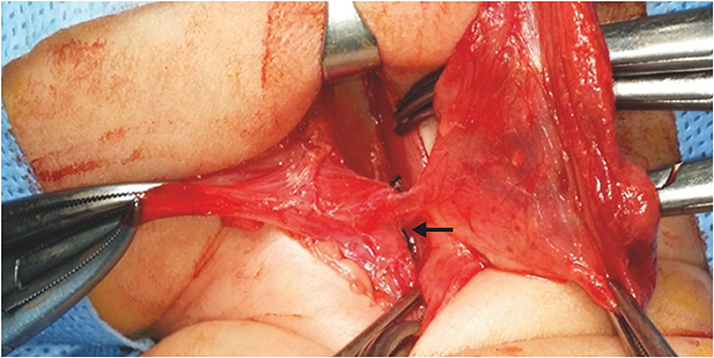

Fig. 2

(A) Aspirated cystic fluid is yellowish and turbid and (B) the cyst is unilocular.

An otherwise healthy girl born at gestation age of 37+6 weeks, birth weight of 3.74 kg, delivered by Cesarean section was referred to our neonatal intensive care unit (NICU) 4 days after birth with swelling and redness of right neck. At birth, skin tag of the right chin was noted. Swelling and redness of the right neck started 2 days after birth. She was fed with normal formula, about 40 mL two to three times per day. She presented with high fever of 39°C and slight inspiratory distress during feeding. Physical examination showed a firm round mass of 4 cm diameter at the anterolateral aspect of right neck. Initial lab results showed nonspecific findings except increased C-reactive protein levels. Initial ultrasound (US) revealed a 3.6×6.5 cm sized elongated cystic mass, medial to carotid space, lateral to trachea, and extending to the retrothyroidal region, containing fluid level and surrounded by an irregular thick wall with minimal soft tissue infiltrates (Fig. 1A). Computed tomography (CT) showed air-bubbles in the nondependent portion of the mass with anterior displacement of trachea and right thyroid gland (Fig. 1B and C). Based on these findings, the mass was suspected to be a complicated anaerobe infected cystic hygroma. Antibiotics therapy were started and needle aspiration was done. Aspirated cystic fluid was yellowish and turbid. Streptococcus viridans was cultured from the fluid (Fig. 2A). Analysis of the fluid showed white blood cell count of 172,800 and low levels of total cholesterol and triglyceride. Feeding was initiated from postoperative 1 day, and size of the cyst started to increase rapidly after needle aspiration, returning to its previous size within two days. Excision of the cyst was done on the 7th day of hospitalization (Fig. 2B). Feeding was reinitiated on postoperative day 1. Pus discharge drained from the neck wound on postoperative 4th day and it contained milk-like substance right after feeding. Esophagography was performed on postoperative day 8, revealing a hairline fistulous communication from the right pyriform sinus to the cyst, suggesting a pyriform sinus fistula due to 4th branchial cleft anomaly (Fig. 1D). Once gastric tube feeding was initiated, size and drainage from the cyst started to decrease. A follow-up esophagography after 15 days demonstrated obliteration of the fistula tract and bottle feeding was started. She was discharged from the hospital after 1 week of bottle feeding, showing no signs of recurrence.